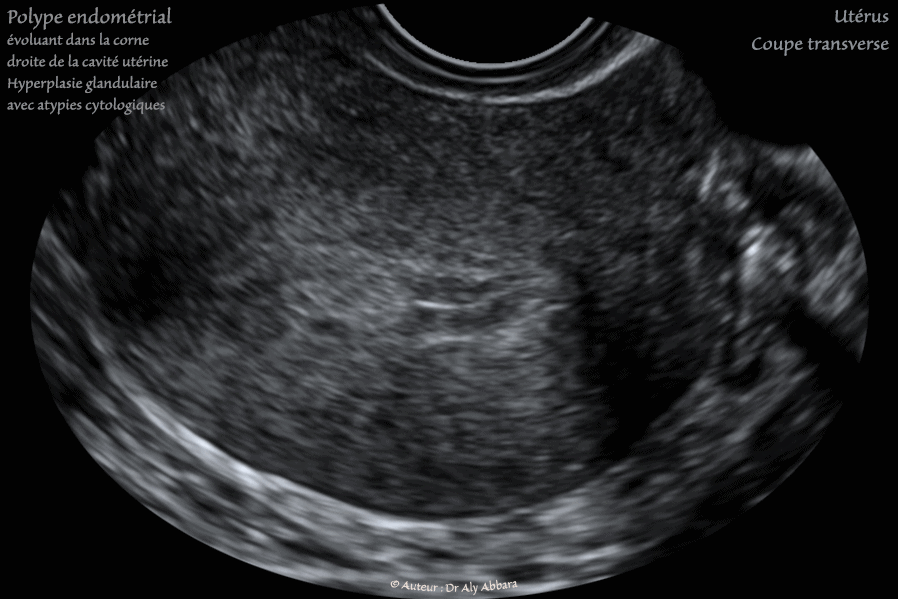

Utérus : Polype endométrial de structure hyperplasique glandulaire simple et complexe avec un foyer d'atypies cytologiques nucléaires :

• Images échographiques montrant (sur une coupe frontale, puis des coupes para-sagittale droite et transverse) la présence au fond utérin, dans la corne droite, la présence d'une formation polypoïde mesurant 14 x 9 x 8,4 mm (soit 0,6 cm3).

L'endomètre lors de la réalisation de cette échographie était en phase proliférative (11° jour du cycle menstruel).

La ligne de vacuité utérine présente une solution de continuité au niveau du site de l'insertion du polype endométrial qui paraît comme une formation ovoïde plus échogène que l'endomètre juxtaposé.